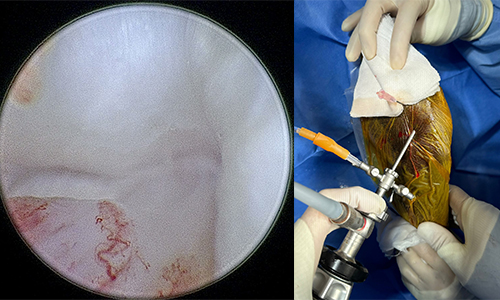

관절경 Arthroscopy 관절

관절경은 작은 절개를 통해 관절 내부에 카메라(관절경)를 삽입하여 병변을 직접 확인하고, 치료하는 최소침습 수술입니다.

주요 적용증은 십자인대 파열, 연골 손상, 관절 내 이물 등 입니다. 정확한 진단과 동시에 치료가 가능해 수술 효과가 높고 회복이 빠르며, 통증과 출혈이 적다는 것이 큰 장점입니다

관절경

관절경 수술 장면 이미지

관절경 장비 및 시술 장면 이미지